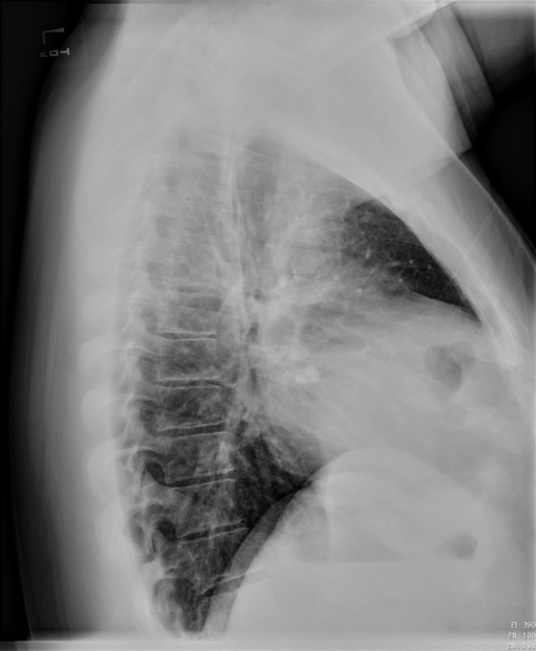

Look for ‘blunting’ of the costophrenic angles on PA projection and posterior costophrenic sulcus on lateral projection. As much as 300-500cc of fluid may not be seen on PA projection, but seen on lateral projection.

Pleural Effusion on Lateral View